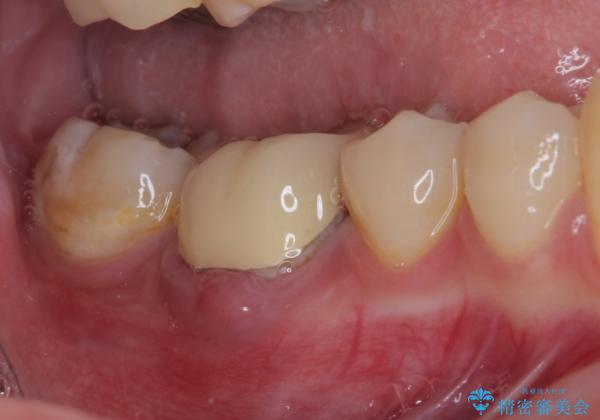

- 奥歯の歯肉から定期的に膿が出てくるとのことで来院された患者様です。

根管治療後は症状を確認し、速やかにオールセラミッククラウンにて補綴治療を行うこととしました。